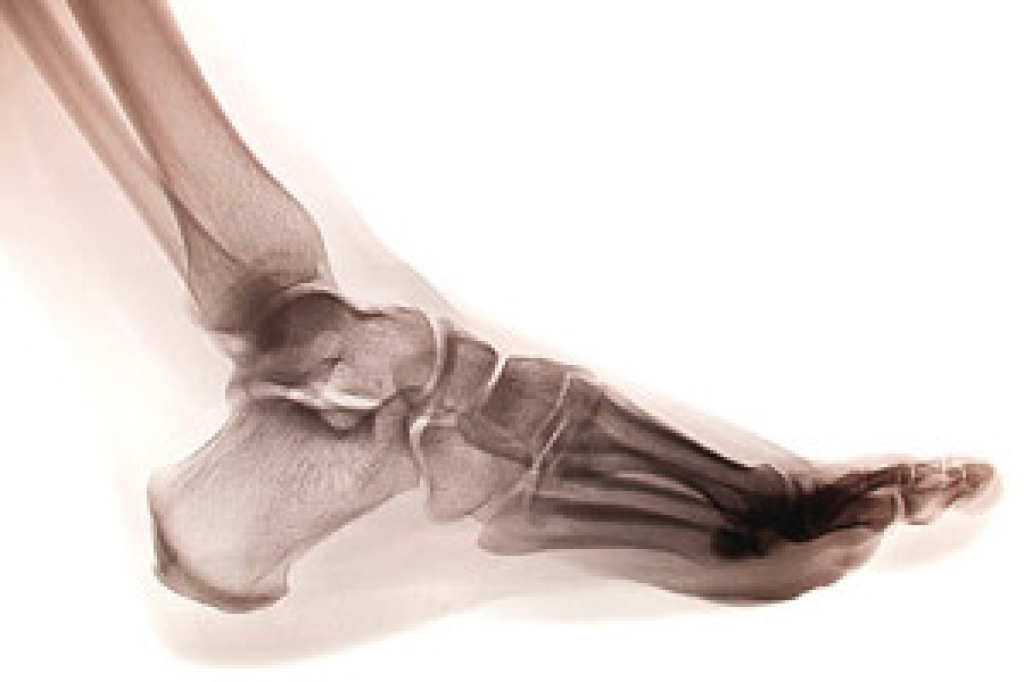

A stress fracture is a common athletic injury. It often involves the long bones in the foot that are known as the metatarsal bones. When a stress fracture occurs, which is also referred to as a hairline fracture, it can cause pain and discomfort. It is often difficult to walk on the affected foot, and relief may come from elevating the foot. It can happen when runners increase their speed and distance too fast. Additionally, people who run for long distances at a time may experience a stress fracture. Wearing shoes that fit correctly may decrease the risk of getting this type of fracture. Some people have existing medical conditions that may increase the risk of getting a stress fracture. These can include osteoporosis, arthritis, diabetes, or a vitamin deficiency. A diagnosis is typically performed by having an X-ray taken, and then proper treatment measures are taken. If you feel you have a stress fracture, it is strongly suggested that you schedule an appointment with a podiatrist who can help you to manage this ailment.

Stress fractures occur when there is a tiny crack within a bone. To learn more, contact Dr. Gerald Perelman from Ohio. Our doctor can provide the care you need to keep you pain free and on your feet.

Stress fractures are the result of repetitive force being placed on the bone. Since the lower leg and feet often carry most of the body’s weight, stress fractures are likely to occur in these areas. If you rush into a new exercise, you are more likely to develop a stress fracture since you are starting too much, too soon. Pain resulting from stress fractures may go unnoticed at first, however it may start to worsen over time.